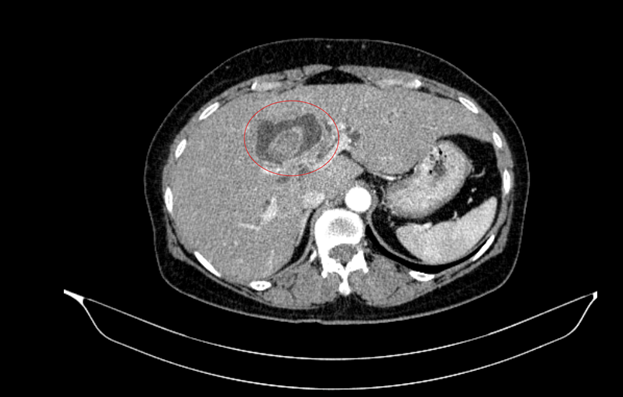

Hình ảnh sỏi đường mật tạo ổ áp xe gan - đường mật gan trái( vòng tròn màu đỏ). Giãn nhẹ đường mật trong gan hai bên. Dày thành nhẹ ngã ba đường mật trên phim chụp cắt lớp vi tính.